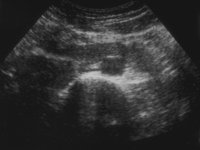

Bei einer jugendlichen Patientin kam es in Folge eines aberrierenden Gefäßes zum Harnstau im linksseitigen Hufeisennierenanteil mit Ausbildung eines fieberhaften Harnwegsinfektes. Unter der Diagnose eines aszendierenden, fieberhaften Harnwegsinfektes wurde die Patientin stationär aufgenommen, nach antibiotischer Therapie, parenteraler Flüssigkeitsapplikation und Bettruhe entfieberte die Patientin. Die Diagnostik ergab in der Sonographie einen Harnstau im linken Nierenanteil mit Verdacht auf Hufeisenniere (Abbildung 4).